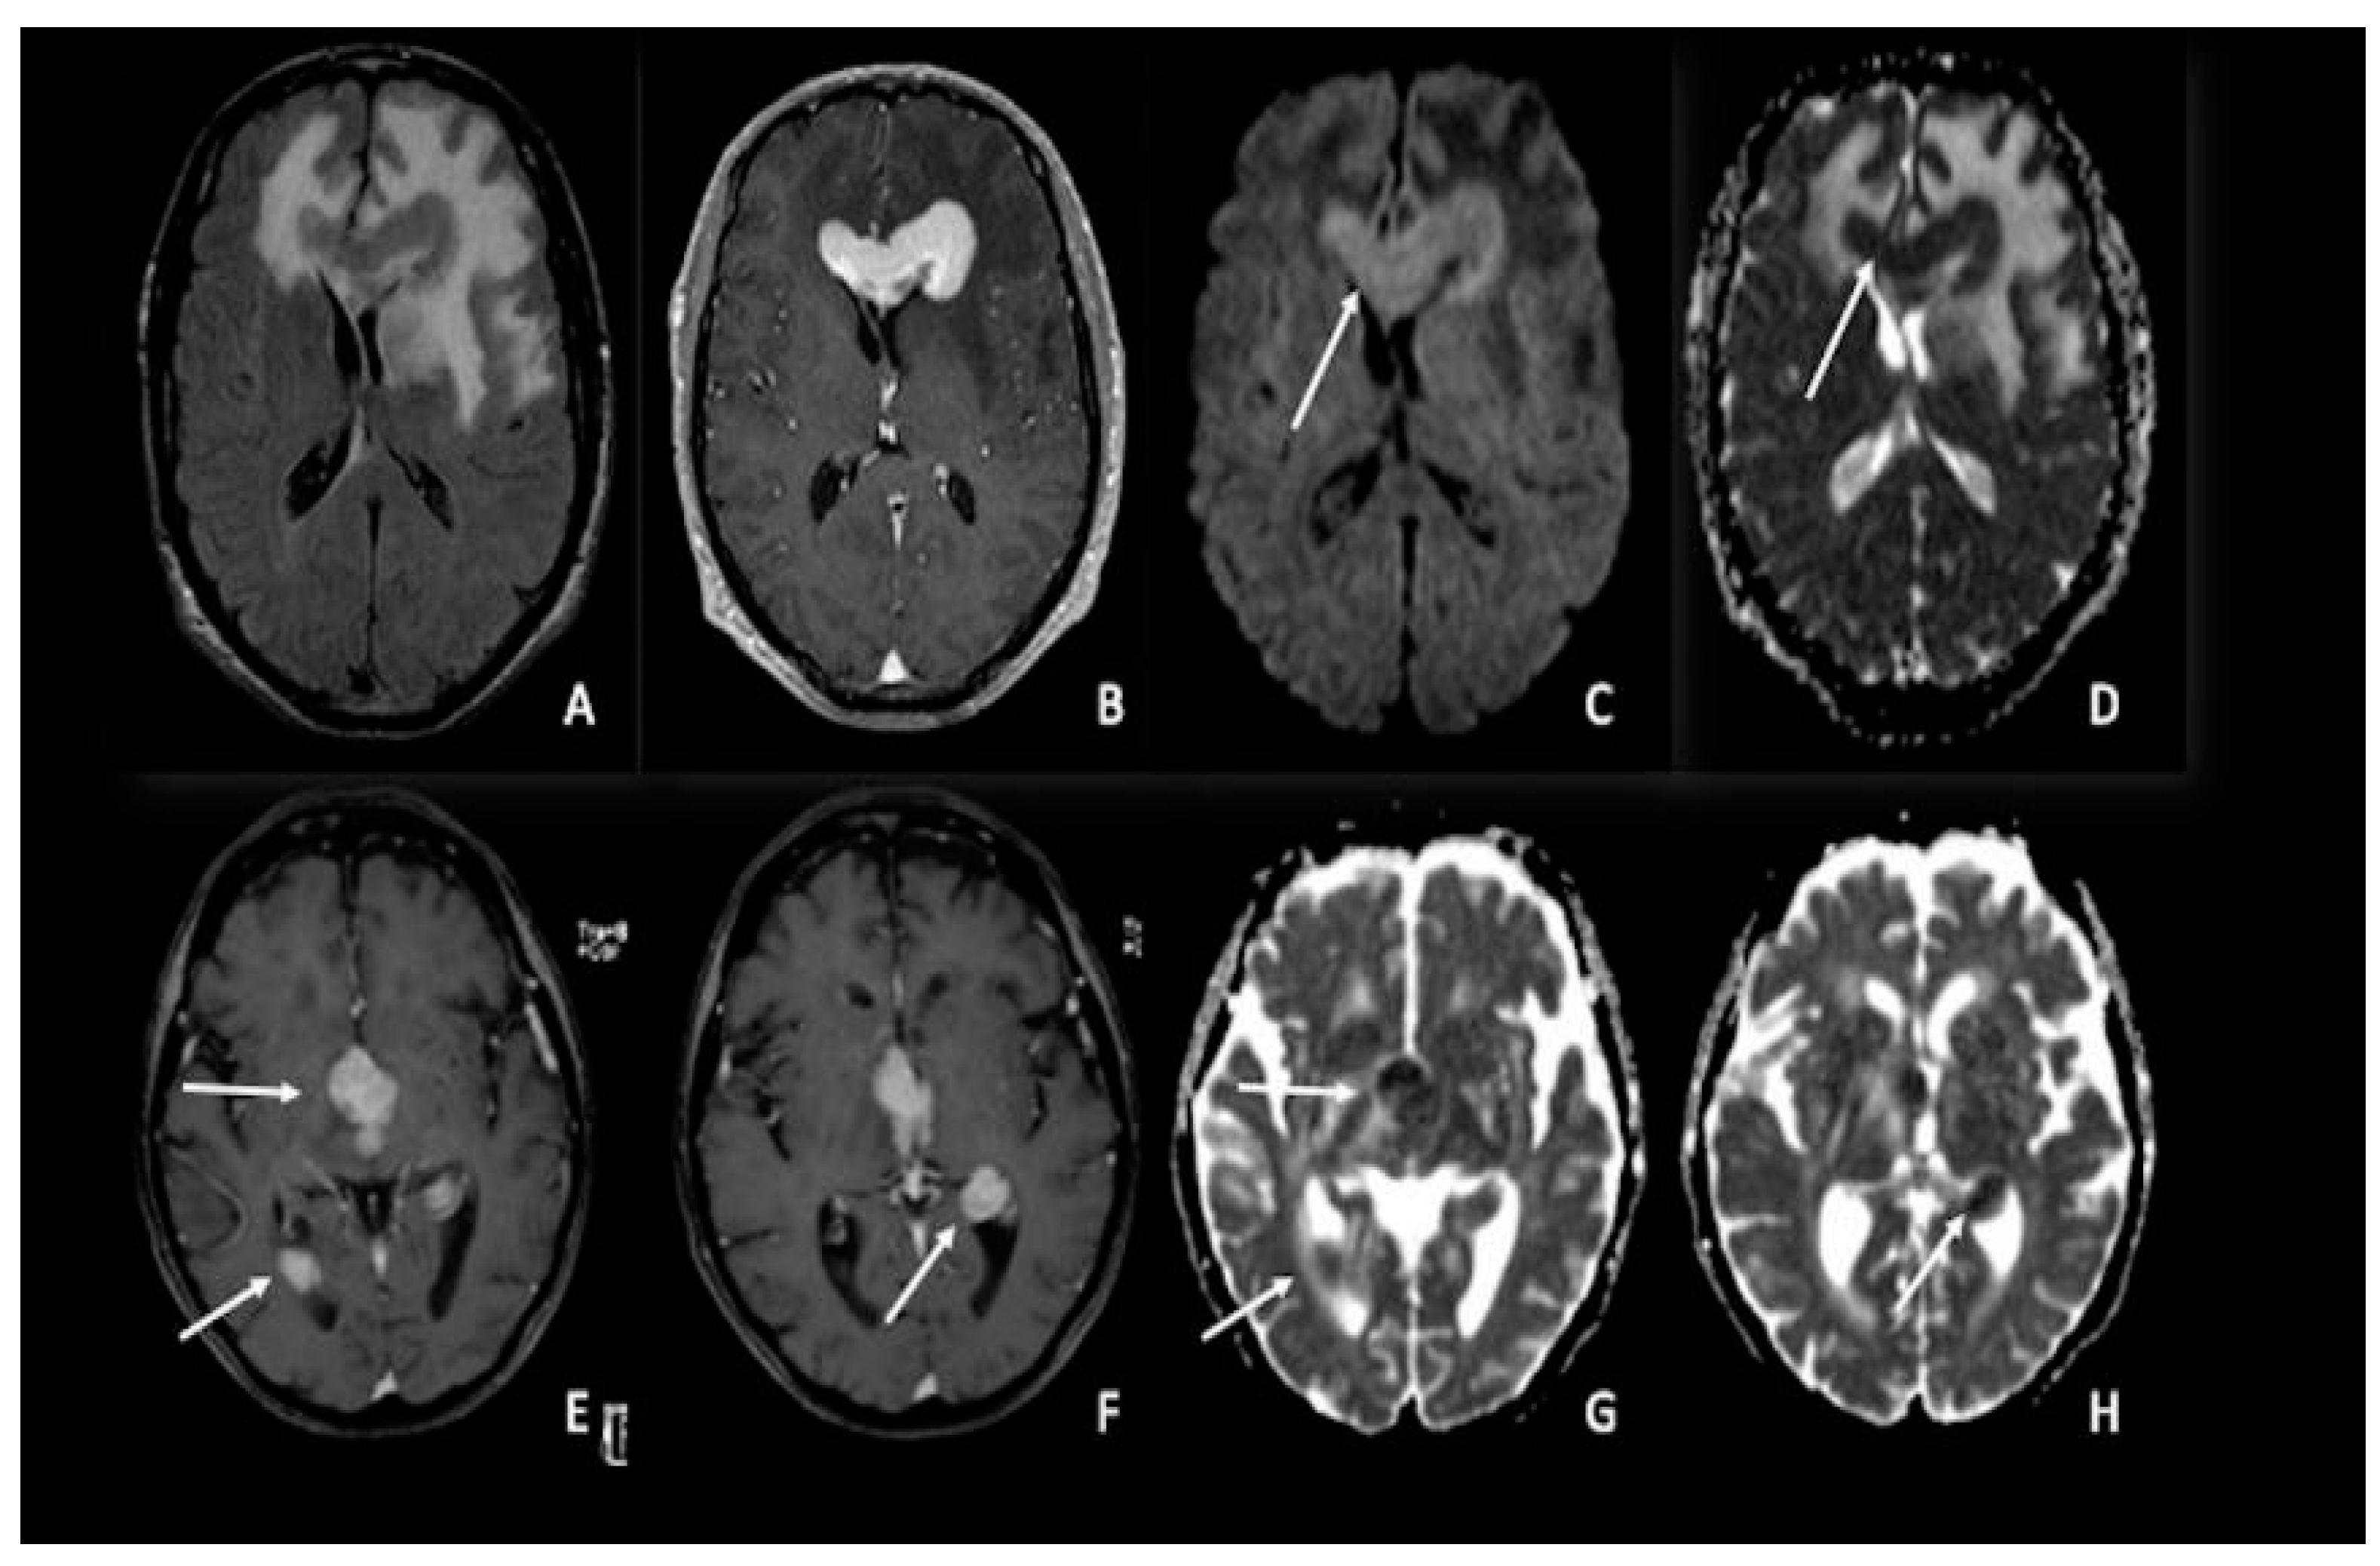

4. Lymphomas

6. Meningiomas and Vestibular Schwannomas

7. Metastasis

8. Gliomas vs. Metastasis